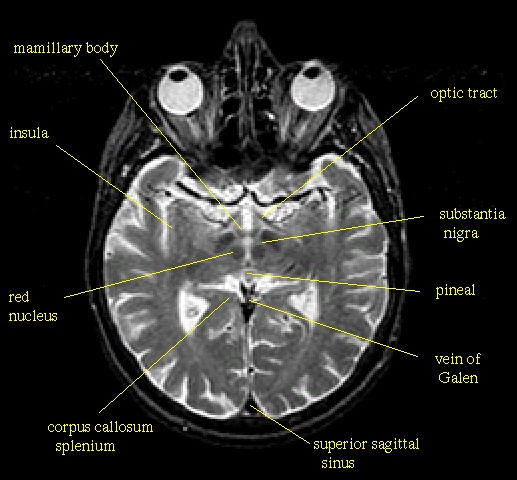

Schneidet man das Gehirn etwa in Höhe der Ohren bzw. dicht unter den Augen horizontal auf, dann ergeben sich das folgende Schnittbild (eine Computertomogramm- bzw. CT-Aufnahme), das nochmals die beiden Kortex-Teile, aber auch jenes schon angesprochene 'Breitbandkabel' - den corpus callosum - zeigt: